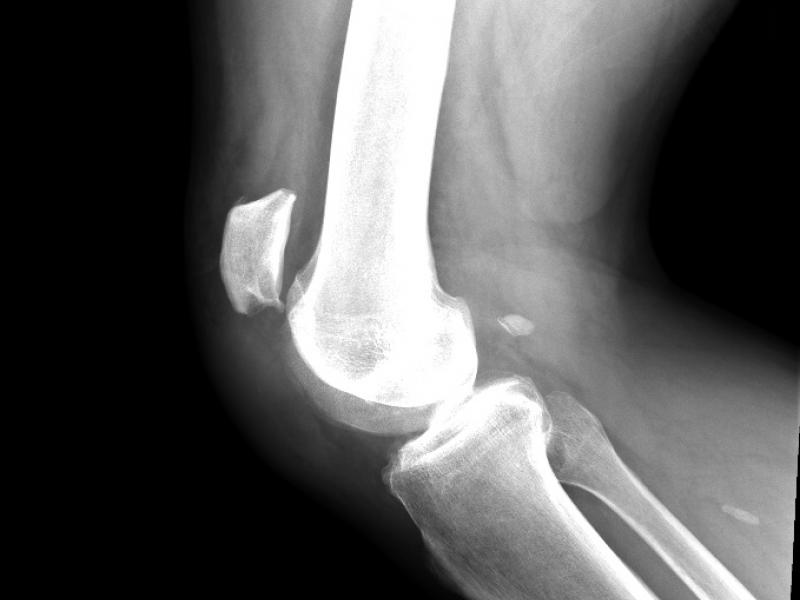

A 59 yo male presents after fall from standing with right